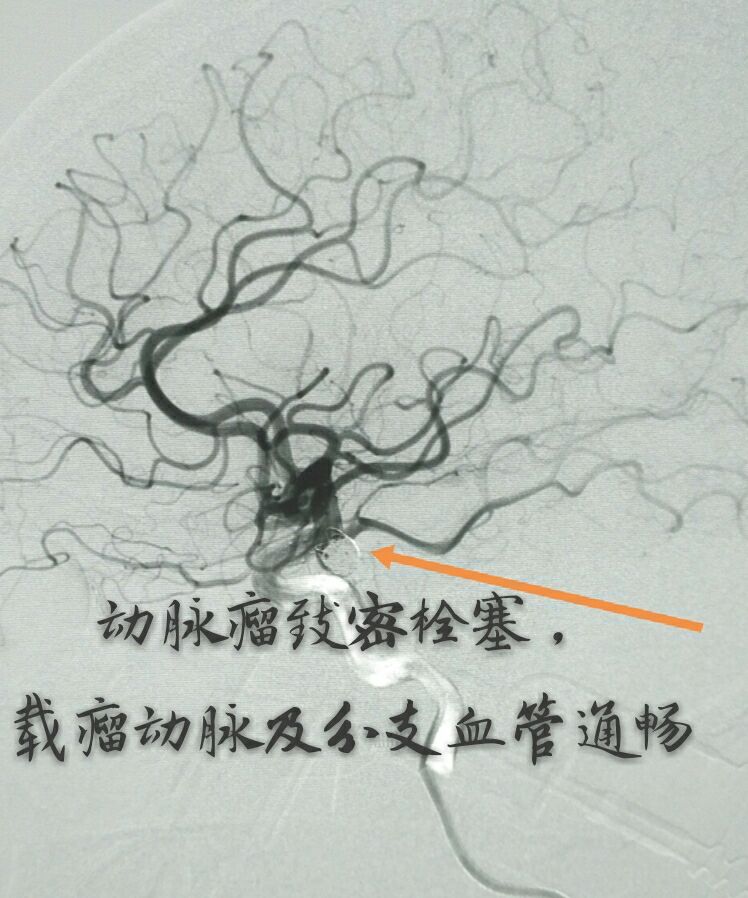

病例十:老年男性患者,间断性头痛1年,DSA示左侧颈内动脉后交通段动脉瘤,后交通动脉从瘤颈部发出

支架打开,首圈完美成栏

最终动脉瘤致密栓塞,载瘤动脉及后交通动脉通畅